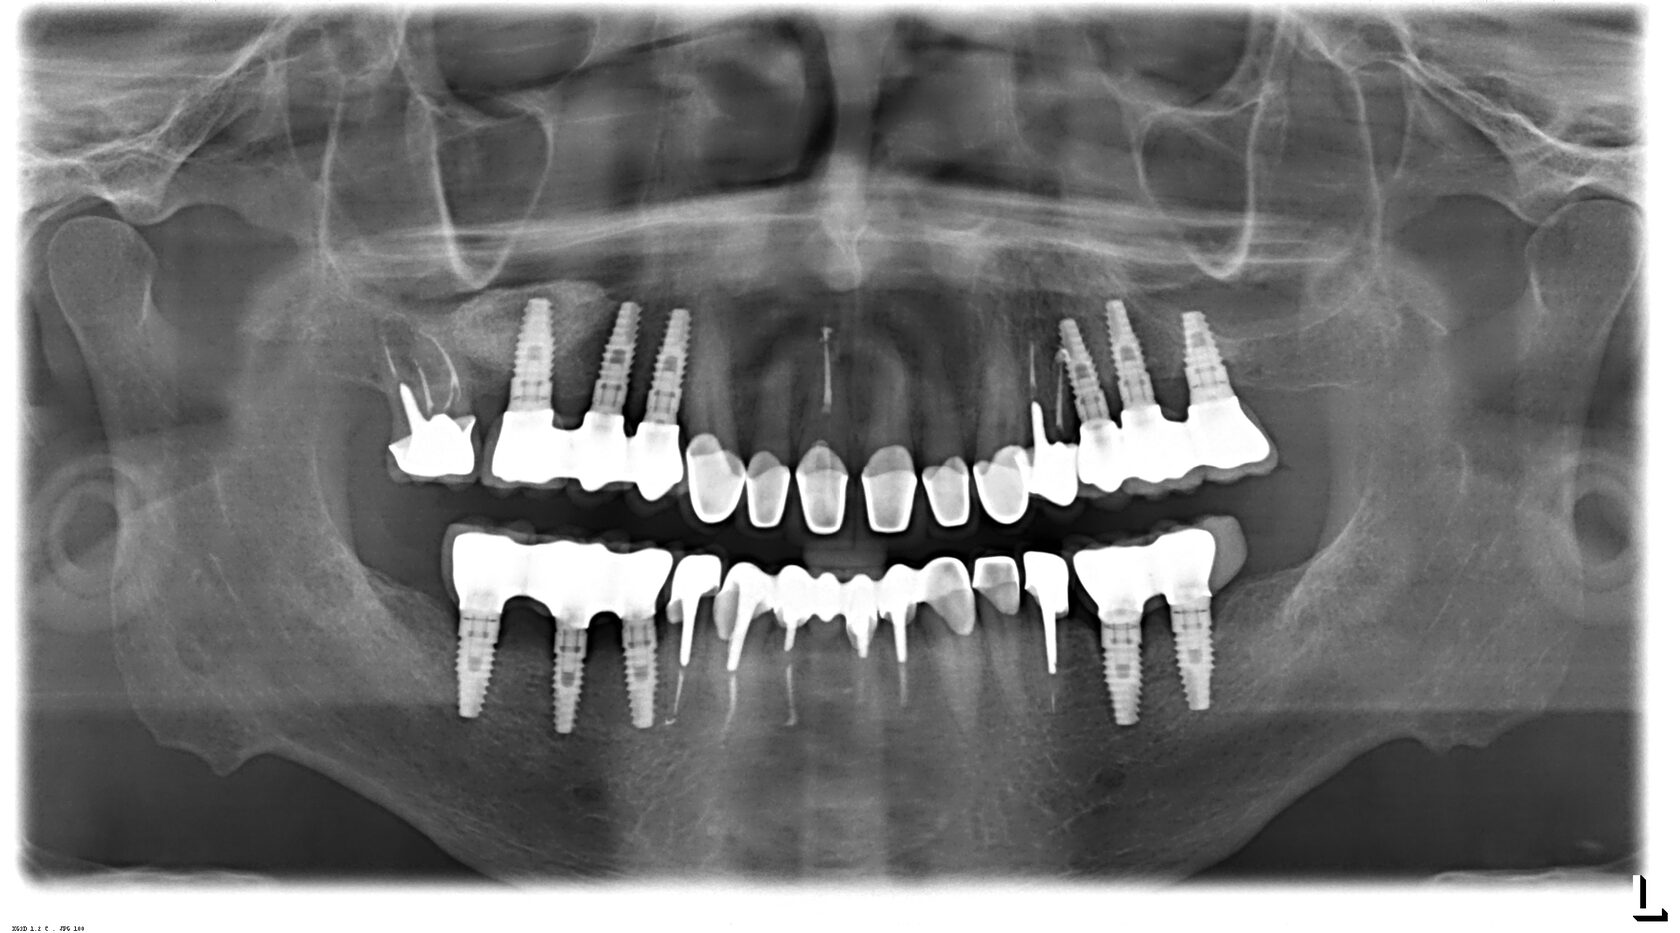

Панорамный рентген зубов — это одномоментное изображение челюстей, которое дает возможность оценить состояние зубов, определить их соотношения, выявить изменения в корнях и околозубных тканях, обнаружить дефекты челюстных суставов.

Обзорный снимок зубов может потребоваться протезисту, ортодонту, пародонтологу. Полученные данные помогут специалисту не только поставить диагноз, но и составить подробный план лечения.

Ортопантомограф — высокотехнологичное рентгеновское оборудование, которое позволяет сделать снимок зубов панорамного типа. Основу аппарата составляют рентгеновский излучатель и цифровой датчик. В результате плавного перемещения вокруг головы пациента получается изображение, на котором видны сразу все зубы на обеих челюстях.